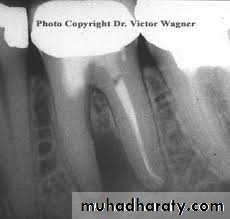

- Difficulty of retreatment:

Presence of silver cone within the canal.Presence of ceramic crown covering the crown

(to overcome these problems surgical intervension is indicated or removal of the old root canal filling)